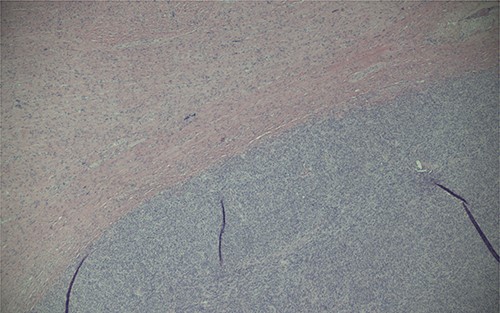

Ultimately, this patient underwent a retropubic radical prostatectomy and bilateral pelvic lymph node dissection. The pathology was reviewed at BC Cancer Centre. A Gleason score 3 + 4 with tertiary 5 prostatic adenocarcinoma was found, involving ~10% of the prostate. Focal extraprostatic extension was found, with no seminal vesicle invasion. Margins were clear, and no malignancy was found in any of the 14 lymph nodes removed. This resulted in a pathologic staging of pT3aN0 (See Figs 1–3). Additionally, a stromal sarcoma was found, measuring 3.2 cm in size, located in the right anterolateral aspect of the specimen. This corresponded to the cystic lesion as seen on ultrasound and MRI. It was found to be arising from a STUMP, and although the tumour grade was favoured to be low, it was mitotically active with up to 10 mitoses per 10 high power field. Margins, again, were found to be negative.

Magnification (40x) of histologic section of prostate, showing STUMP (upper left of image) and adjacent sarcoma (lower right of image).